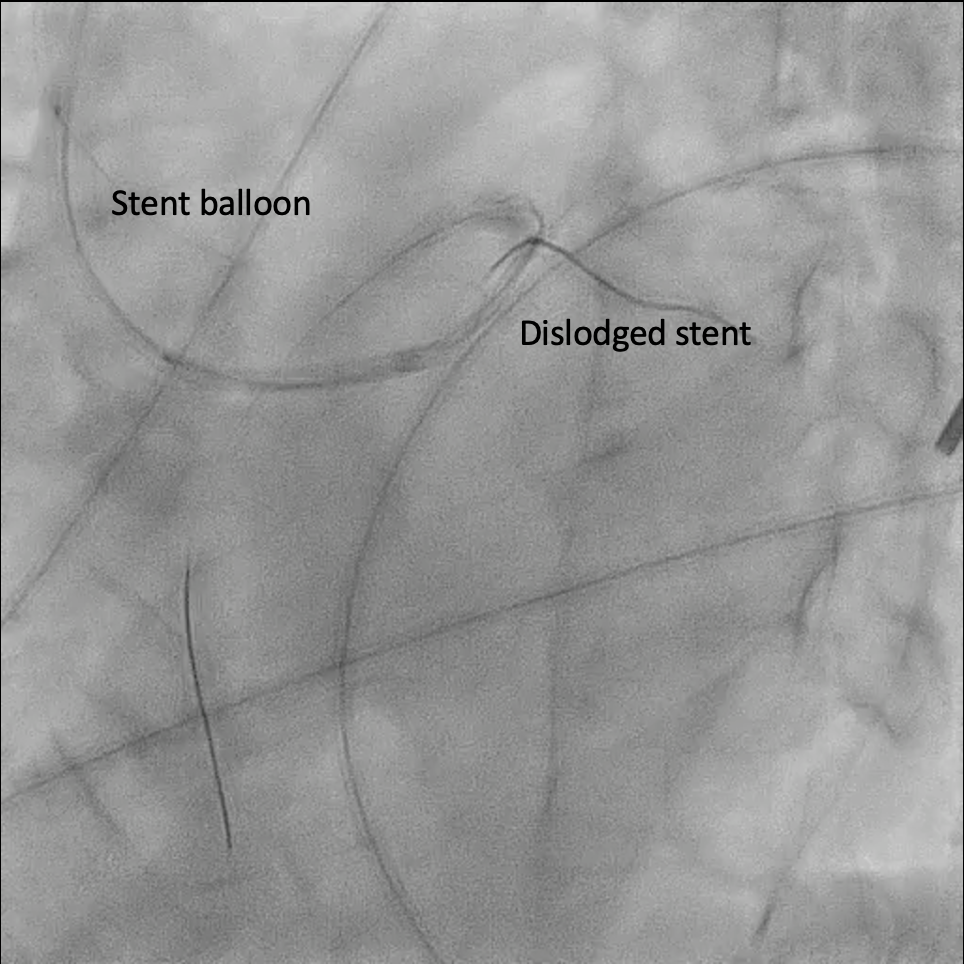

Under IABP (left femoral), PCI via right brachial with 6 Fr EBU 3.5. Runthrough to LAD, Sion Blue to LCX. Predilation of LM/pLAD with 2.0¡¿20 mm balloon; IVUS pullbacks. Further dilatation with 2.5¡¿20 mm NC for mLAD underexpansion, pLAD, and LM. oLCX de novo and pLCX edge ISR predilated with 2.5¡¿20 mm NC; LCX ISR treated with DCB 2.5¡¿20 mm. Szabo technique attempted for LM–LAD with a 3.0¡¿24 mm DES; the undeployed stent dislodged during repositioning and was deployed at the dislodgement site. IVUS showed 2–3 struts protruding into the aorta from the LM ostium and incomplete pLAD coverage. Post-dilation with 3.5¡¿20 and 2.5¡¿20 mm NC; DCB 3.0¡¿20 mm for pLAD uncovered plaque and mLAD proximal edge ISR. Final CAG: TIMI 3 flow.At 3 months, staged PCI via right radial with 6 Fr EBU 3.5. Sion Blue ES to distal LAD. IVUS: mLAD stent underexpansion (MSA <2.0 mm©÷); wire not through struts. IVL 3.5¡¿12 mm initially could not cross LM; after guide exchange (JL 3.5, then EBU 3.0/3.5), IVL advanced to mLAD and delivered 100 shocks, producing a ring crack and area gain. Further dilation with 3.0¡¿20 and 3.5¡¿20 mm NC. IVUS: pLAD type B dissection without flow limitation. DCB 3.5¡¿40 mm to p–mLAD. LM ostial stent further dilated with 3.5¡¿20 mm. Final CAG: TIMI 3 flow.

Timing matters as much as technique—operator fatigue and suboptimal midnight conditions can silently amplify risks in complex PCI. Past success can bias current judgment; repeating a previously effective technique may overlook new anatomical nuances. Guiding catheter engagement is double-edged: while it enhances support, it compromises precision at the ostium. Preparation should anticipate rare complications, not just manage common ones.